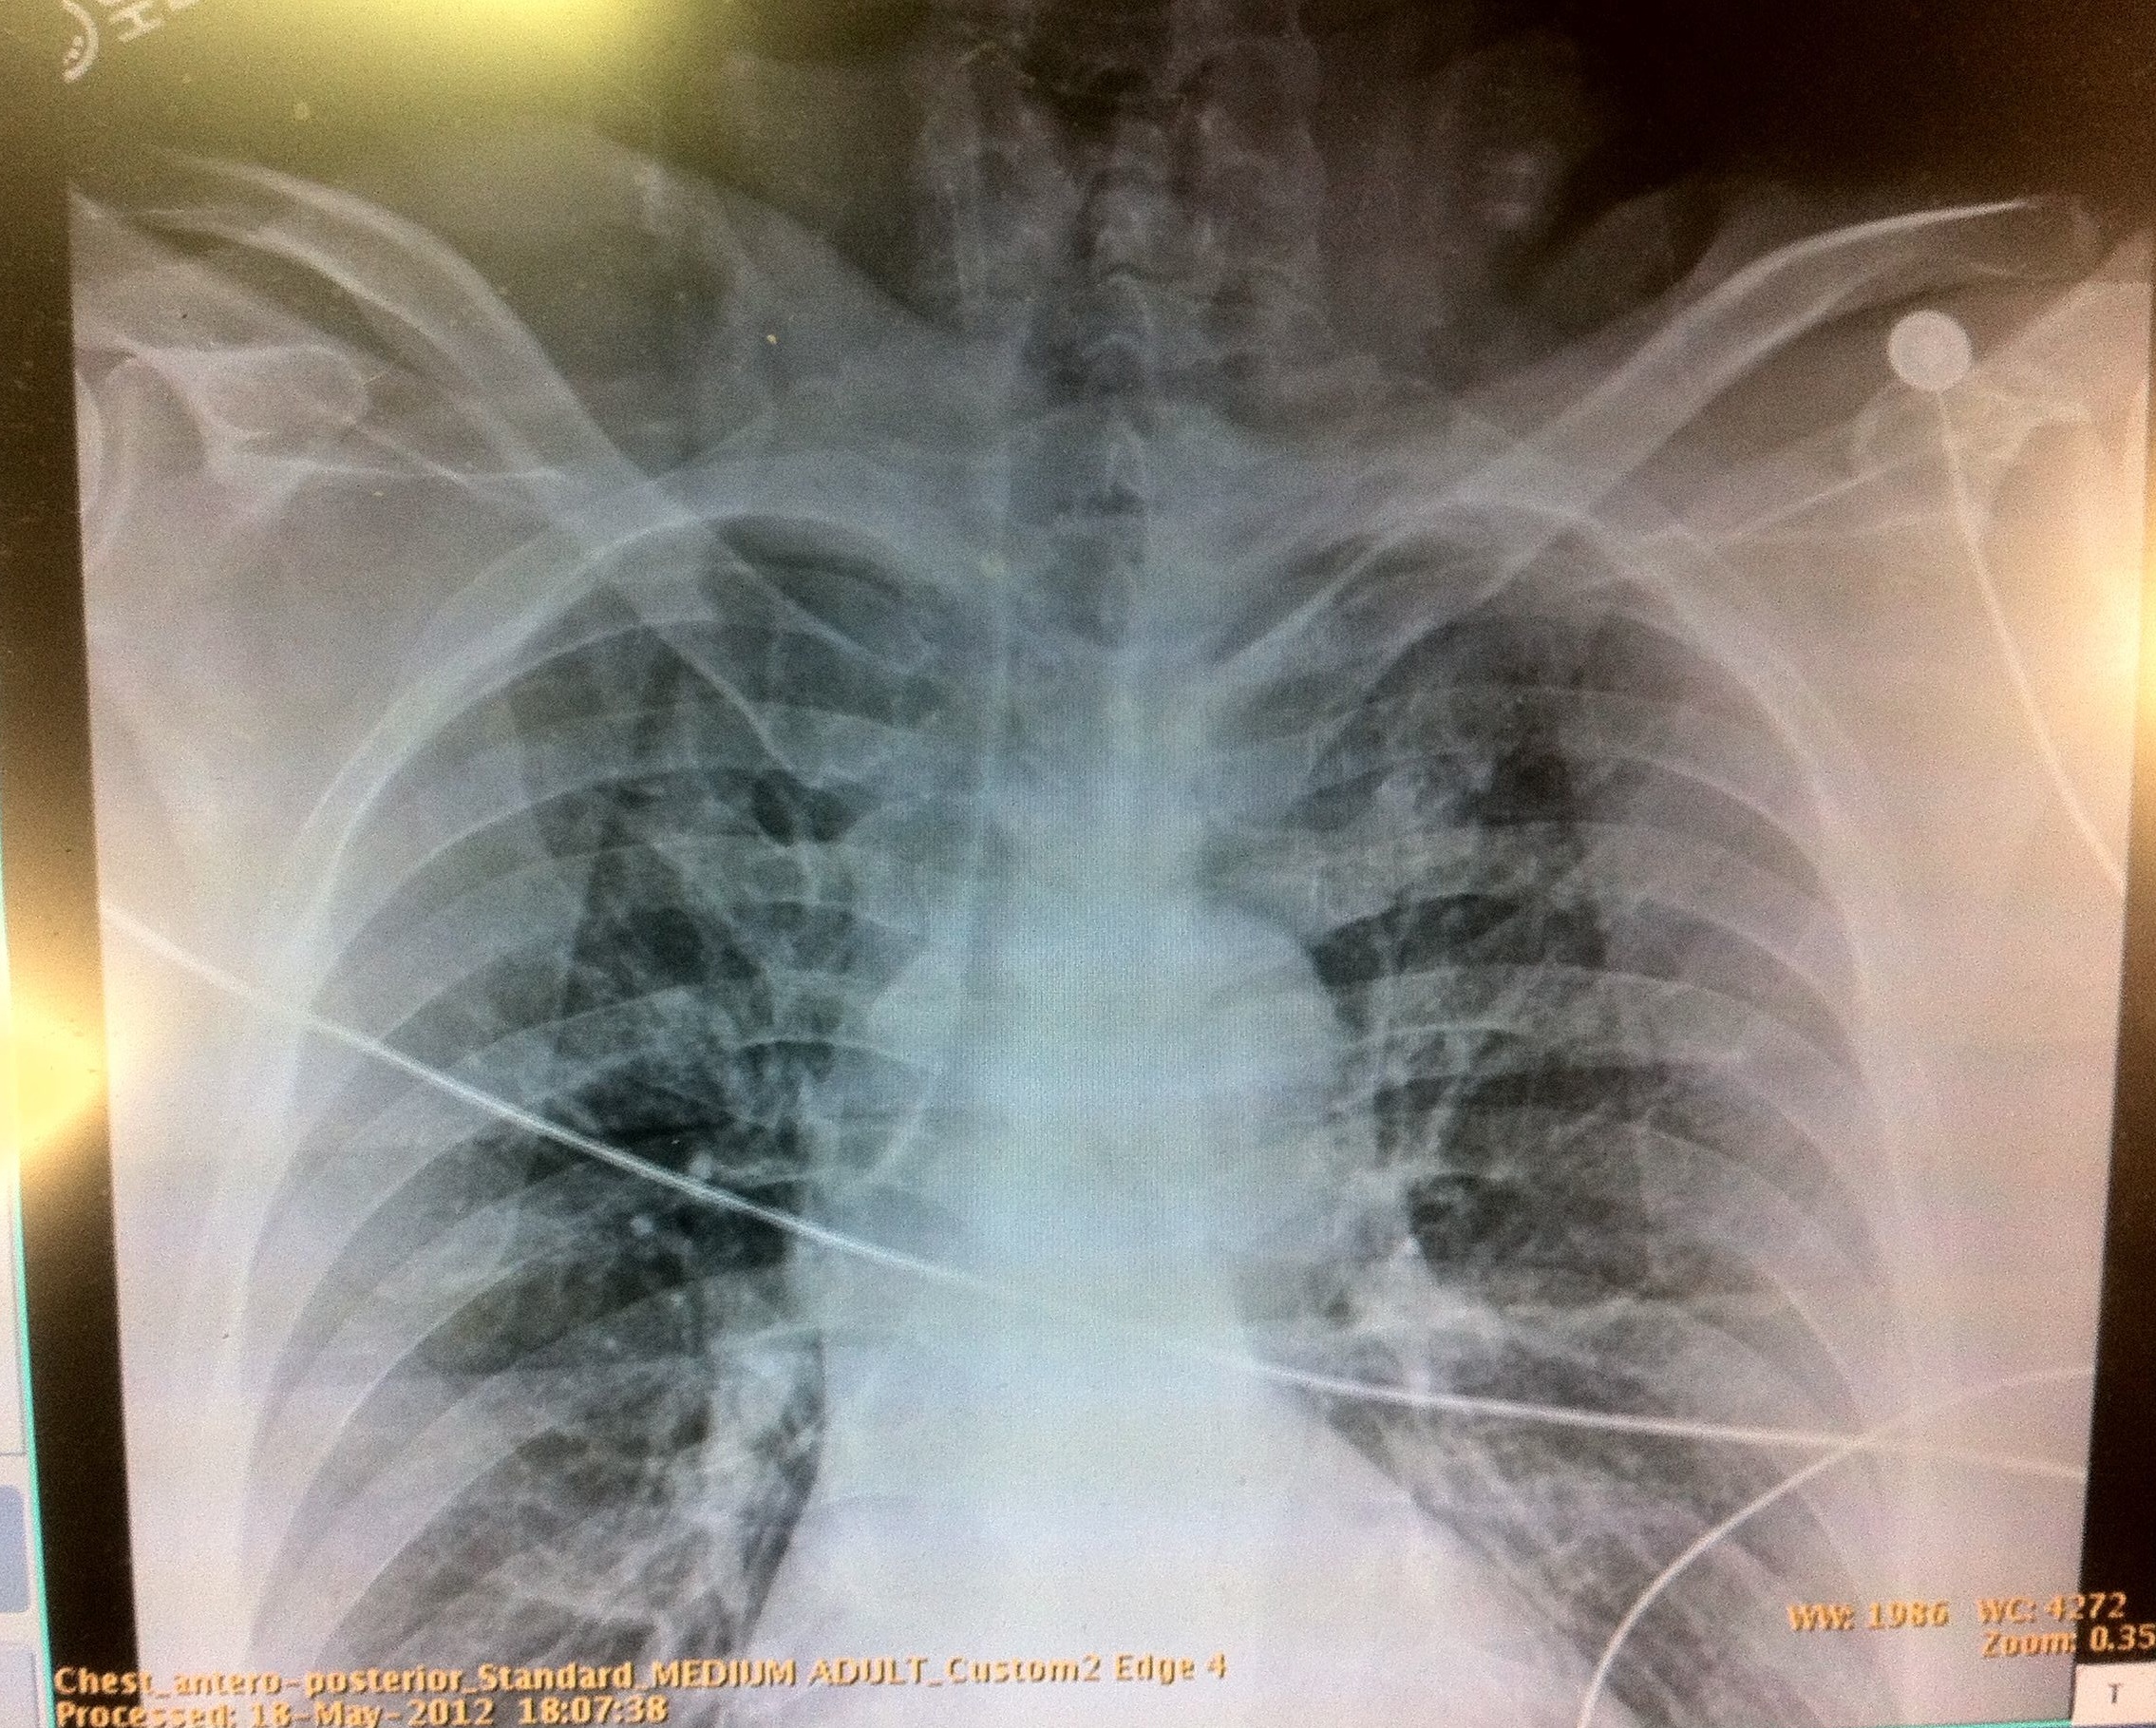

So, this case that I just had the other day is an example of an “oldy but goody” reason why bedside ultrasound rocks, especially in the blunt trauma victim with multiple injuries. 40 year-old motorcycle helmeted driver going moderate speed was T-boned by a car and fell onto his left side. He c/o severe left leg pain and mild left lower back pain, with STABLE (and yes, I mean, stable/normal/not worrisome vitals – HR 72, RR 16, BP 148/90, O2 sat 97%RA) with a clear primary trauma survey, and a secondary that revealed a small abrasion on his cheek, no left sided chest wall tenderness, nontender abdomen, no pelvis instability, an obvious deformed open fracture of his left tibia/fibula, and left lower posterior rib cage tenderness without crepitance or bruising. An E-FAST was done… which includes evaluation for intrathoracic, intraperitoneal and pericardial free fluid with the addition of bilateral lung views for pneumothorax evaluation. Using the linear probe, and placing it on the anterior chest wall, 2nd intercostal space, mid-clavicular line, with the indicator toward the patients head, you can screen for pneumothorax (absence of lung sliding and comet tail artifacts come down from the pleural line which you would normally see). This was his Lung view on the left:

This was his lung view on the right: